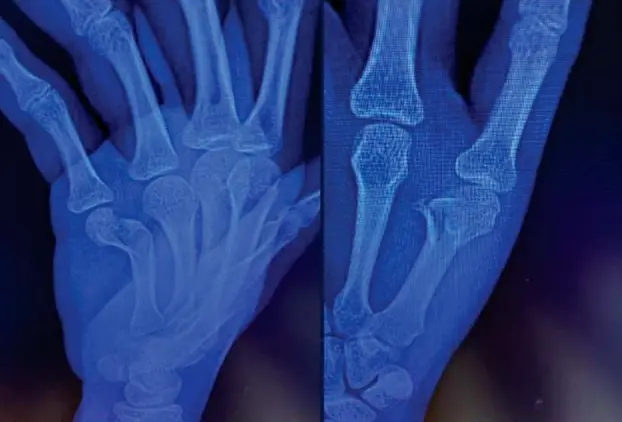

1. Percutaneous Screw Fixation for Metacarpal Head Fractures

微信图片_2026-04-27_153600_027.png

微信图片_2026-04-27_153538_627.png